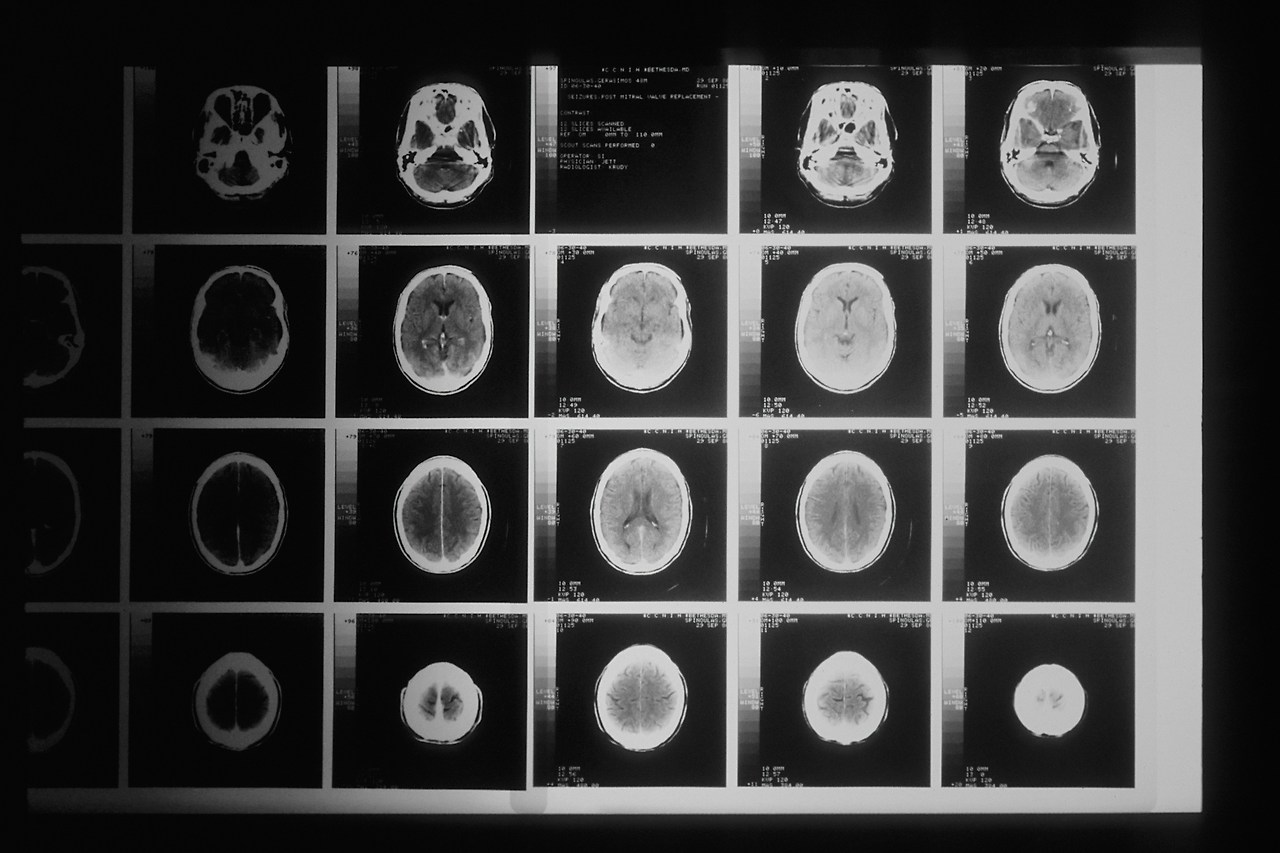

national-cancer-institute-BDKid0yJcAk-unsplash.jpg 출처: unsplash

먼저 서울아산병원 연구팀은 도파민 신경세포 상태를 확인하는 DAT PET 영상을 학습한 생성형 AI 모델을 개발했다. 이 모델은 초기 파킨슨병과 본태성 떨림을 최대 99.7% 정확도로 구분했으며, 파킨슨병과 유사 질환 간 감별에서도 높은 정확도를 보였다.

특히 이 기술의 핵심은 단순 진단을 넘어, 질병의 진행 과정을 ‘영상 형태로 예측’할 수 있다는 점이다. 확산모델 기반 학습을 통해 사람의 눈으로는 포착하기 어려운 미세한 신경 변화까지 분석하고, 이를 바탕으로 향후 변화를 시각화한다.